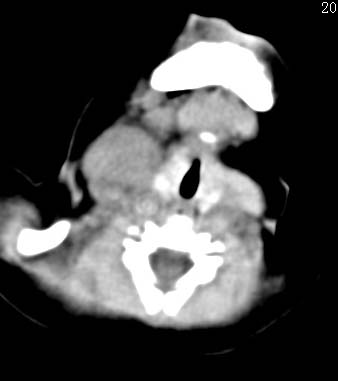

以下是引用zjzjr在2008-12-18 11:20:00的发言:[br]右颈部软组织肿块,性质待定(神经源性肿瘤等排),上下径较长,不太支持肿大淋巴结.